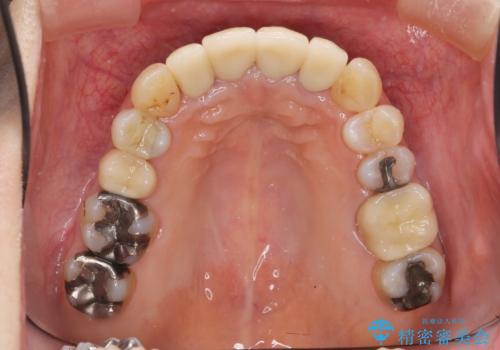

矯正治療が終わったのちに、精度の高いセラミックを装着することでより安定した噛み合わせとなり審美性も兼ね備えた口腔内状態で治療を終了し、今後のメンテナンスを行っていくことができます。